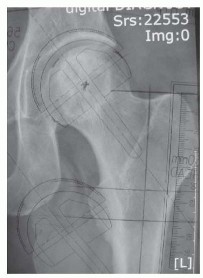

DEFINITION Varus intertrochanteric osteotomy involves the reorientation of the proximal femur in order to imp…